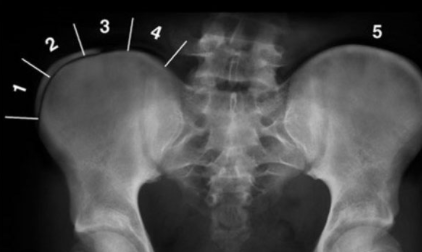

Qual é a importância da Linha de Risser?

A Linha de Risser é um indicador radiológico usado para avaliar a maturação esquelética e estimar o crescimento restante do paciente, auxiliando no planejamento do tratamento.